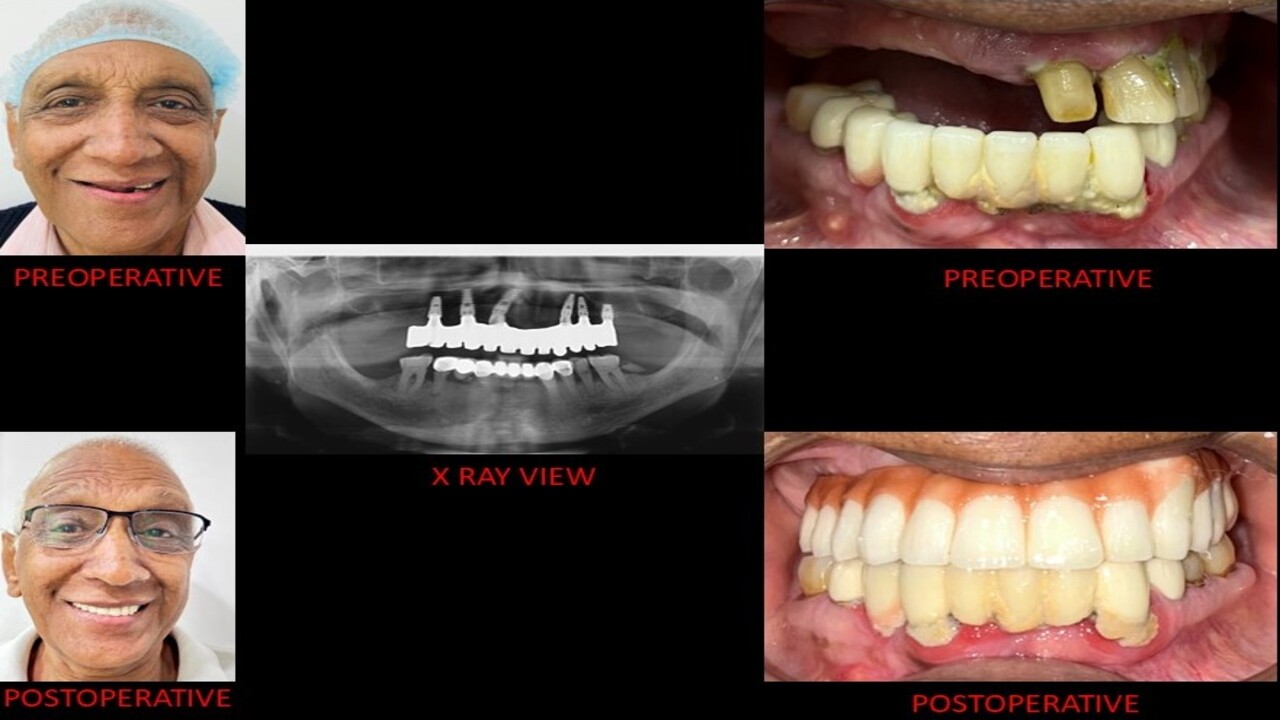

At Smile Dental Care Centre, we invite you to discover our exceptional dental care services in Delhi. We proudly hold the title of the best dental clinic in East of Kailash, Delhi and Faridabad, with a dedicated team of skilled dentists committed to preserving your oral health and enhancing your smile.

With two convenient locations in East of Kailash and Faridabad, we are even more accessible to serve your needs. Our state-of-the-art facility offers a wide range of services, including routine check-ups and advanced cosmetic and restorative procedures. Prioritizing your comfort, we employ the latest technology and gentle techniques for a pain-free experience.

At Smile Dental Care Centre, your health is our main concern. Our best dentist in Faridabad and Delhi provide friendly and personalized care to fit your needs and give you a happy, healthy smile. We’re also at the forefront of dental technology, using the latest advancements to ensure the best possible care for you. Get in touch today to set up your appointment!